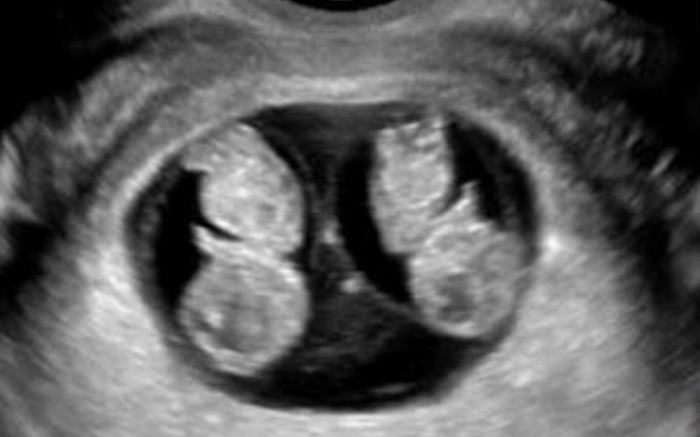

Tuy nhiên mới đây, Bệnh viện Phụ Sản Hà Nội đã tiếp nhận một trường hợp thai phụ 23 tuổi, mang thai lần đầu, thai tự nhiên, kết quả siêu âm cho thấy chung một bánh rau, hai buồng ối từ tuần thai thứ 8.

Thai phụ đến đơn vị Can thiệp bào thai - Bệnh viện Phụ Sản Hà Nội thăm khám ở tuần thai 16 vì có một thai phù. Sau khi hội chẩn, siêu âm và chọc ối phát hiện thai A phù thai, giới tính trên siêu âm là nữ, kiểu gen nữ Turner (45,X).

Thai B bình thường về mặt hình thái và giới tính trên siêu âm là nam, kiểu gen nam (46,XY). Các xét nghiệm di truyền chuyên sâu khác cũng đã được thực hiện và chứng minh rằng 2 thai này chung 1 trứng nhưng có kiểu gen khác nhau.

Hình ảnh trường hợp thai nhi bất thường. Ảnh: BV